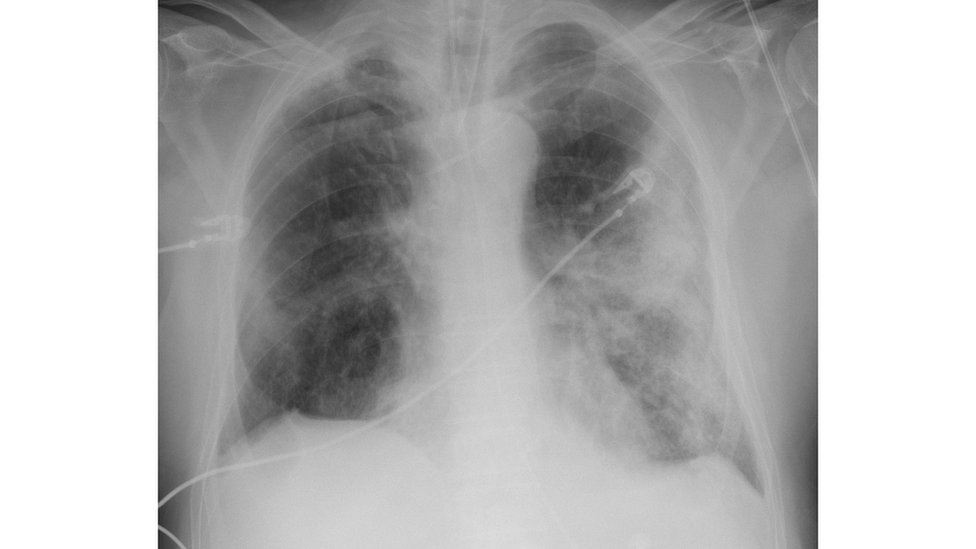

Ova široka rasprostranjenost ACE-2 razlog je zašto Kovid-19 izaziva toliko širok dijapazon simptoma. Od infekcije u nosu, preko gubitka čula mirisa, do zapaljenja pluća, koje izaziva težak kašalj.

Zarazivši gornje disajne puteve, nos i gornji deo pluća, zapaljenje izaziva kašalj i kijanje, što rapidno širi bolest. Za to vreme, zaraza donjih disajnih puteva može da izazove ozbiljne, potencijalno fatalne, probleme sa disanjem.

Profesor Farzan kaže da naučnici sada imaju dokaze da deca, na koje odlazi manje od 2 odsto bolesti, imaju manje ACE-2 receptora u nižim delovima pluća od odraslih.

„To znači da će deca biti manje sklona bolesti, makar onoj vrsti teške upale pluća koju doživljavaju odrasli“, kaže profesor Farzan.

Međutim, ona i dalje imaju visok broj receptora u gornjim delovima pluća, objašnjava on.